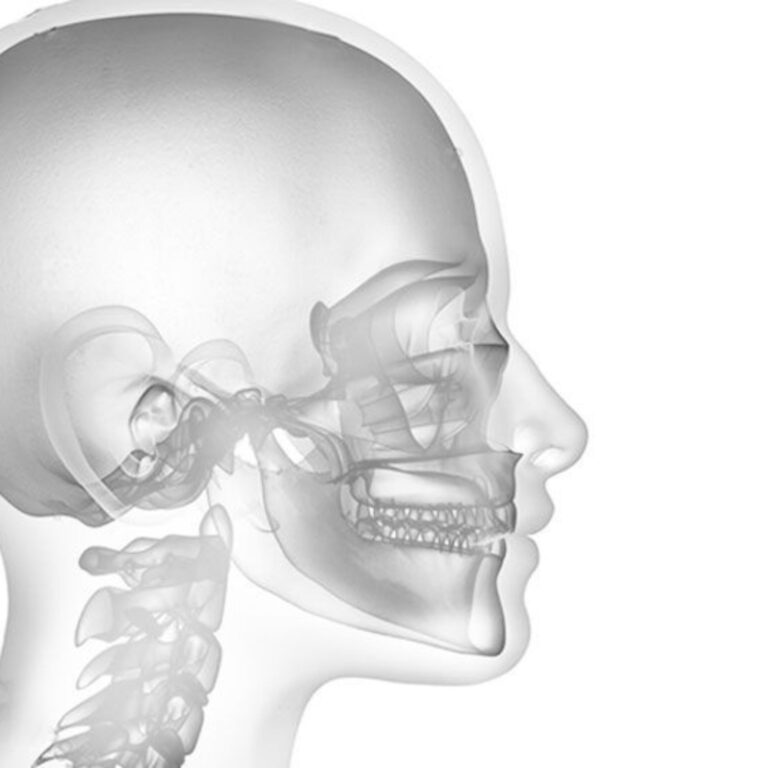

Le bruxisme nocturne n’affecte pas uniquement les dents : il peut provoquer des douleurs musculaires

au visage, des tensions au niveau de l’articulation temporo-mandibulaire et des difficultés dans les

mouvements de la mâchoire. La qualité du sommeil peut également se détériorer, générant des micro-

réveils et un cercle vicieux qui favorise la réapparition de la parafonction.

Symptômes articulaires

• Crépitements, « clics » ou bruits de l’articulation temporo-mandibulaire

• Raideur ou difficulté à ouvrir complètement la bouche

• Stabiliser l’articulation temporo-mandibulaire (ATM)

L’ATM peut être particulièrement affectée par le bruxisme, entraînant des bruits articulaires, des blocages ou une gêne à l’ouverture et à la fermeture de la bouche.

L’utilisation d’une gouttière occlusale permet une meilleure répartition des forces occlusales et réduit la surcharge articulaire, améliorant ainsi sa fonctionnalité.

Bruxisme et posturologie

Le bruxisme résulte d’une combinaison de facteurs : stress, tension émotionnelle, malocclusion, troubles de l’articulation temporo-mandibulaire (ATM), mais aussi déséquilibres posturaux au niveau du cou, du dos et du bassin.

Lorsque la mâchoire ne se déplace pas de manière harmonieuse, les muscles masticateurs travaillent de façon asymétrique, générant des tensions qui se répercutent sur l’ensemble de la posture.

Il est essentiel d’évaluer l’ensemble de la chaîne posturale du patient :

• l’appui plantaire

• la position du bassin

• la mobilité cervicale

• l’équilibre musculaire global